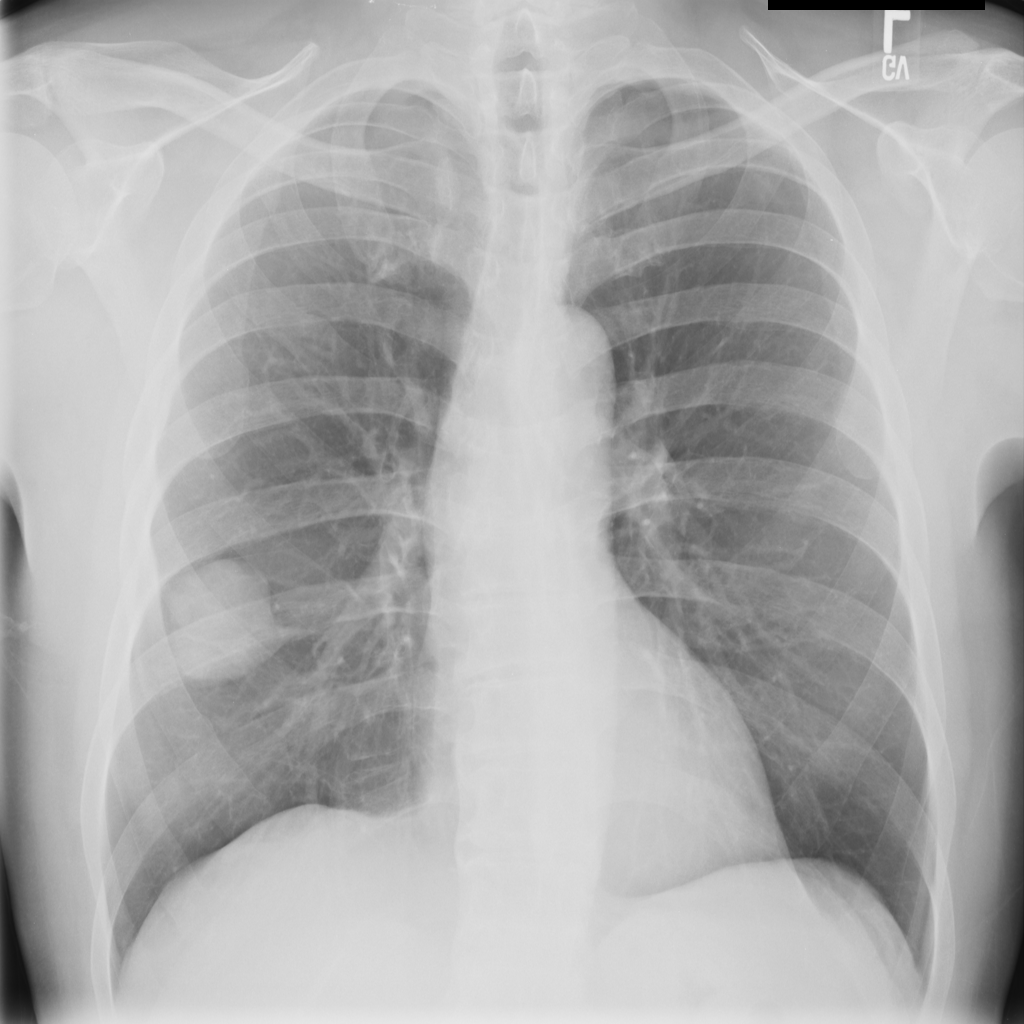

Mass

A mass is a larger focal opacity or lesion seen on the image. It is a descriptive finding that can have several causes and usually needs more imaging or clinical context to characterize.

PAT-50E5 · IMG-008Mass

PAT-50E5 · IMG-008

PA